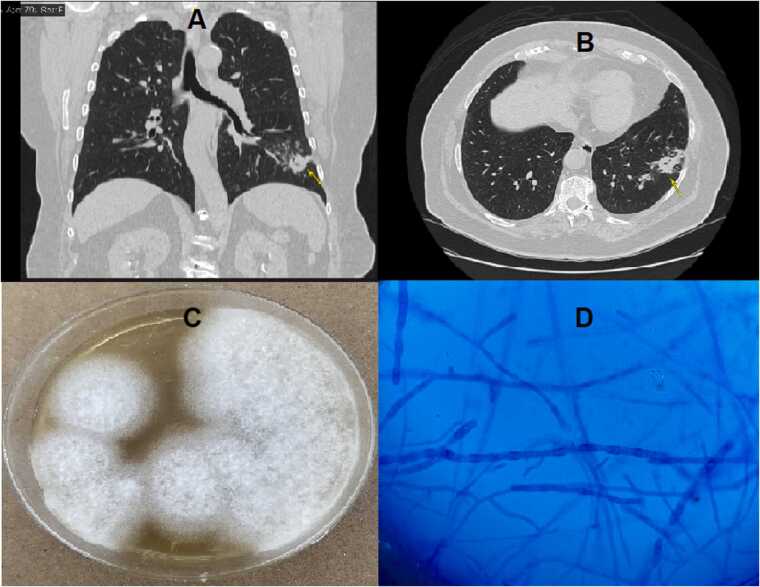

Coccidioidomycosis is a potentially serious but poorly studied mycosis in Ecuador. It is not a notifiable infection; therefore, its true incidence and prevalence in Ecuador remain unknown. Because primary lung disease due to coccidioidomycoses is typically self-limiting, it does not usually require treatment. Here, we present the first case of Coccidioides posadasii infection in an asymptomatic patient with diabetes without a history of travel to an endemic area. This is the first case reported in Ecuador in the last half-century.